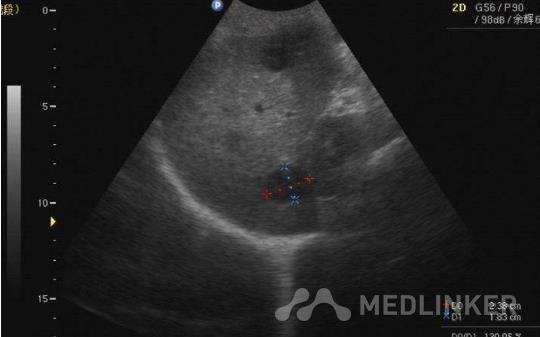

查体:体温为36.5 ℃,心率为72次/分,呼吸节律为20次/分,血压为110/85 mmHg。患者神志清楚,皮肤及巩膜明显黄染,结膜苍白,未见肝掌及蜘蛛痣。腹平软,无明显压痛,上腹部可触及一大小约4 cm×5 cm的肿块,界限较清,活动度差,有轻压痛,移动性浊音阴性。其余无明显异常。  辅助检查:白细胞 6.12×10^9/L,中性粒细胞 72.1%,血红蛋白 81g/L,血小板 205×10^9/L。肿瘤标志物:癌抗原 35.62 U/ml,癌胚抗原 2.74 μg/L。腹部CT:胰头区肿物,大小约6.8 cm×5.6 cm,呈不均匀强化;胆总管明显扩张,肝脏多发占位,考虑为转移瘤。CT示胰头巨大肿块,肝脏多发占位,考虑为胰腺癌肝转移。

诊断:胰腺癌肝转移。 治疗:B超引导下胰头肿物穿刺活检后3天,患者病理结果显示为:胃肠间质瘤。肝功能改善后予以吉西他滨化疗。术后,给以复方曲肽注射液用于防治肿瘤患者化疗后周围神经毒性。